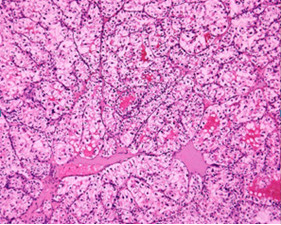

Volver a los detalles del artículo Metástasis cutáneas por un adenocarcinoma renal